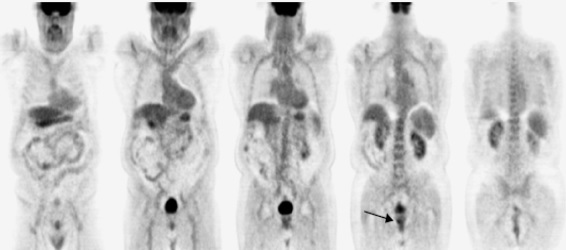

Se nos remitió el paciente al servicio de Medicina Nuclear para realizar una exploración PET-TAC con FDG. La exploración se realizó en un tomógrafo Biograph 6 (Siemens, Alemania) habiendo estado el paciente en ayunas (8h), hidratado (1 litro de agua) y mediante la administración intravenosa de 370 MBq de 18F-FDG. La adquisición de las imágenes comenzó después de un periodo de reposo de 50 minutos, rastreando desde las órbitas hasta el tercio medio de los muslos (4 minutos/cama). El volumen adquirido se reconstruyó por el método iterativo (4 iteraciones y 8 subconjuntos), con un zoom de 1 y en una matriz de 168. La corrección de atenuación se realizó con una fuente de rayos X incorporada al equipo y la adquisición de una imagen inicial por el método de modulación de dosis. En el análisis del estudio no se encontraron hallazgos sugestivos de recidiva local ni metástasis a distancia (fig. 1). No obstante, se descubrió un depósito focal patológico del trazador, de contornos bien delimitados y situación periférica en el lóbulo prostático derecho, de 12 mm de diámetro y elevada actividad (SUV 6,8), sospechoso de malignidad, que obligaba a proseguir investigando (fig. 2).